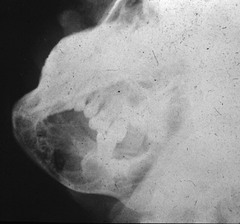

sialolith

-obstruction in the gland hard nodule in soft tissue at a salivary gland -calcification of material -can be seen radiographically